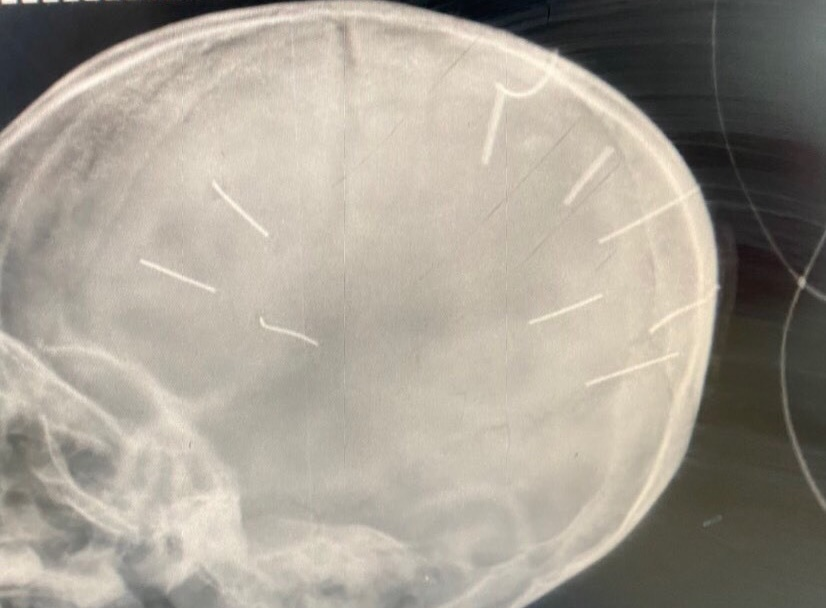

Hình ảnh phim chụp cho thấy hộp sọ của bệnh nhi có 9 đinh. (Ảnh: BVCC)

Đáng chú ý, tại Bệnh viện Đa khoa Xanh Pôn, kết quả phim chụp cắt lớp cho thấy bệnh nhi Đ.N.A. có hình ảnh như bị đinh bắn vào sọ. “Có 9 chiếc đinh. Bệnh nhân đang trong tình trạng rất nặng, đe doạ tử vong cao”, BS Kiên cho biết thêm.